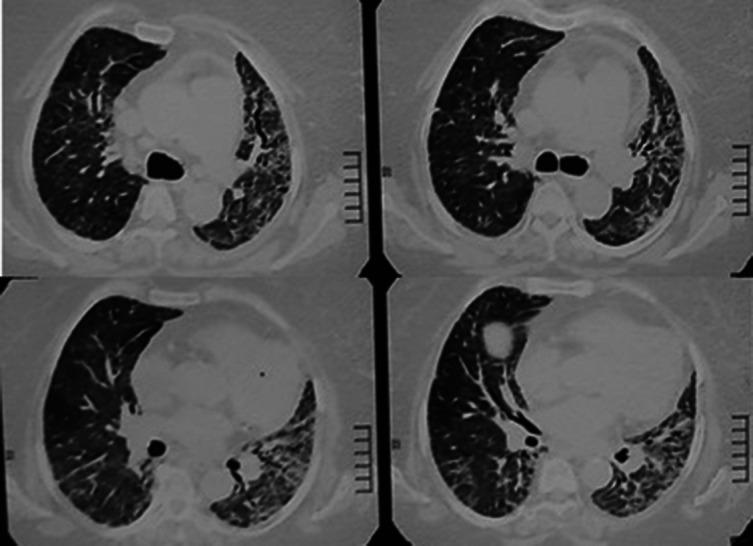

Out of 150 long-COVID patients recruited in the study, about 79% (118), 14% (22), and 7% (10) had a history of mild, moderate, and severe COVID-19, respectively. Fatigue (P = .001), breathlessness (P = .001), tachycardia (P = .002), tachypnea (P < .001), raised blood pressure (P < .001), crepitations (P = .04), hypoxia at rest (P < .001), significant desaturation in 6-minute walk test (P = .27), type 1 respiratory failure (P = .001), and type 2 respiratory failure (P = .001) were found to be significantly higher in the long-COVID patients with a history of severe COVID-19. These patients also had the highest prevalence of abnormal chest X-ray (60%) and honeycombing in computed tomography scan thorax (25%, P = .027).

在该研究招募的150例长新冠患者中,分别约有79%(118例)、14%(22例)和7%(10例)有轻度、中度和重度COVID-19病史。疲劳(P = 0.001)、呼吸困难(P = 0.001)、心动过速(P = 0.002)、呼吸急促(P < 0.001)、血压升高(P < 0.001)、啰音(P = 0.04)、静息时低氧(P < 0.001)、6分钟步行试验中显著氧饱和度下降(P = 0.27)、Ⅰ型呼吸衰竭(P = 0.001)和Ⅱ型呼吸衰竭(P = 0.001)在有重度COVID-19病史的长新冠患者中显著更高。这些患者胸部X线异常(60%)和胸部计算机断层扫描蜂窝状改变(25%,P = 0.027)的患病率也最高。